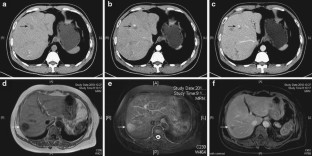

Fig. 2